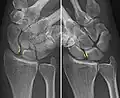

Static scapholunate dissociation -

Dynamic instability: Increased scapholunate distance (between yellow lines) upon ulnar deviation of the wrist, but not otherwise. -